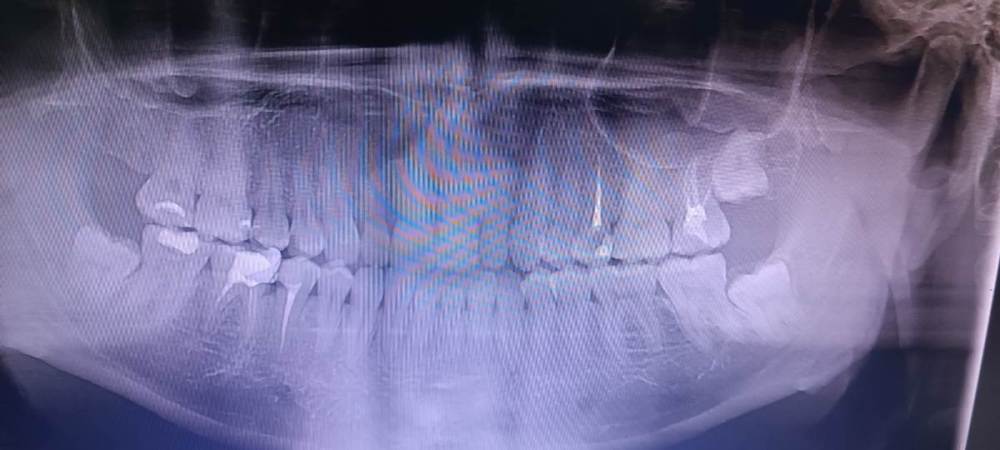

moreman0594 Опубликовано 19 декабря, 2023 Автор Поделиться Опубликовано 19 декабря, 2023 16.12.2023 в 20:38, moreman0594 сказал: У меня такая сложная ситуация, в октябре начались тянущие боли в шее, тяжее наклонять голову в левую сторону и чувство онемения в правой стороне лица, через некоторое время начала болеть десна снизу, там где зуб мудрости. Вся ситуация произошла на работе время вахты, когда приехал домой, сразу пошёл в стоматологию, там мне сделали общий снимок всех зубов, два раза смотрели и сказали, что с зубами все нормально и перенаправили к неврологу. Она меня осмотрела и поставила диагноз неврология троичного нерва. Три недели я ходил к неврологу на лечение, делал разные уколы и пил таблетки, лучше не стало, даже иногда боль усиливалась. В конце третей недели мне лучше не стало и невролог сказала, что мои "полномочия здесь всё", я тебе дала всё возможное лечение. В итоге мне оставалось неделя до отъезда на работу, у меня десна начала болеть сильнее, периодически поднималась температура до 37.2, я сходил еще в три стоматологии мне там так же сказали что с зубом все хорошо. За пару дней до отъезда, я пошёл получаеться уже в 4 стамоталогию, там стоматолог сказал, что не видит признаков воспаления зуба, но если есть желание может удалить, но так как удаление сложное и я уезжаю на крайний север, нужно неделю на восстановление, он мне предложил удалить по приезду, я записался на 25 декабря. По приезду на работу боль в десне стала нестерпимая, я начал принимать сильные обезболивающие. Через некоторое время боль в десне утихла. В итогу на сегодня десна фактически не болит, но онемение лица и шеи так же осталось. Стоит ли мне все таки удалить зуб или причина может быть в чем нибудь другом? P.S. извиняюсь за длинный текст, даюсь кто-нибудь дочитает? Снимок Ссылка на комментарий

Doc Опубликовано 19 декабря, 2023 Поделиться Опубликовано 19 декабря, 2023 Восьмерки, в принципе, уже никогда не прорежутся и пользы от них никакой. Можно удалить хотя бы для исключения причины. Но они расположены довольно близко к нижнечелюстному каналу, поэтому нужно найти очень хорошего хирурга, который возьмется за эту процедуру, да и то всегда есть риски. Ссылка на комментарий

red_butler Опубликовано 19 декабря, 2023 Поделиться Опубликовано 19 декабря, 2023 Здравствуйте, к сожалению качество снимка не позволяет его полноценно интерпретировать. Нужны Кт и очный осмотр. Опишите характер боли, есть ли разница от времени суток, провоцирует что то боль, в каком месте шеи болит? Ссылка на комментарий